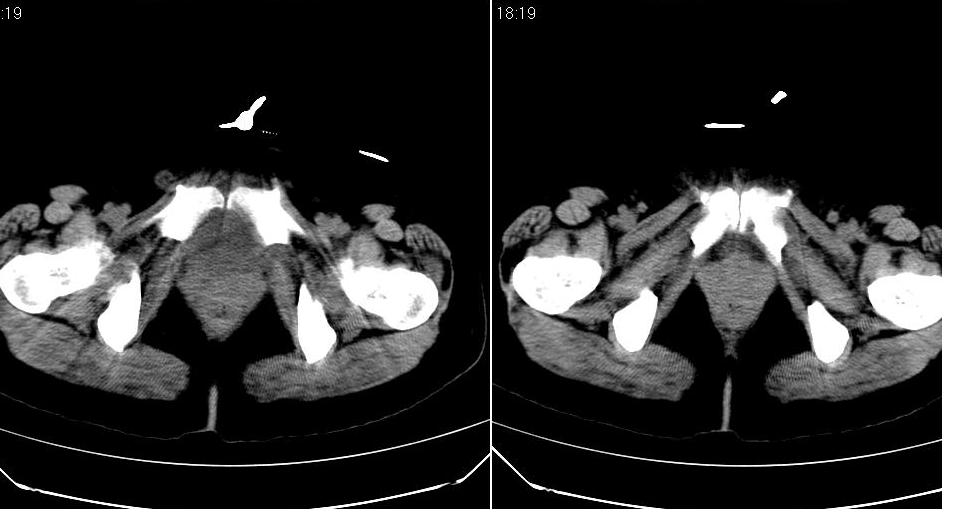

盆腔及腹腔积液,原因待查。

结核性腹膜炎可能,